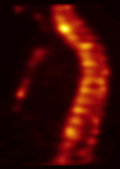

1. Improved imaging results. Through hybrid xSPECT/CT technology, our bone cancer scan is clinically useful compared to SPECT alone because of improved anatomic localisation and diagnostic certainty.

SJMC xSPECT-CT Bone Scan Imaging xSPECT/CT